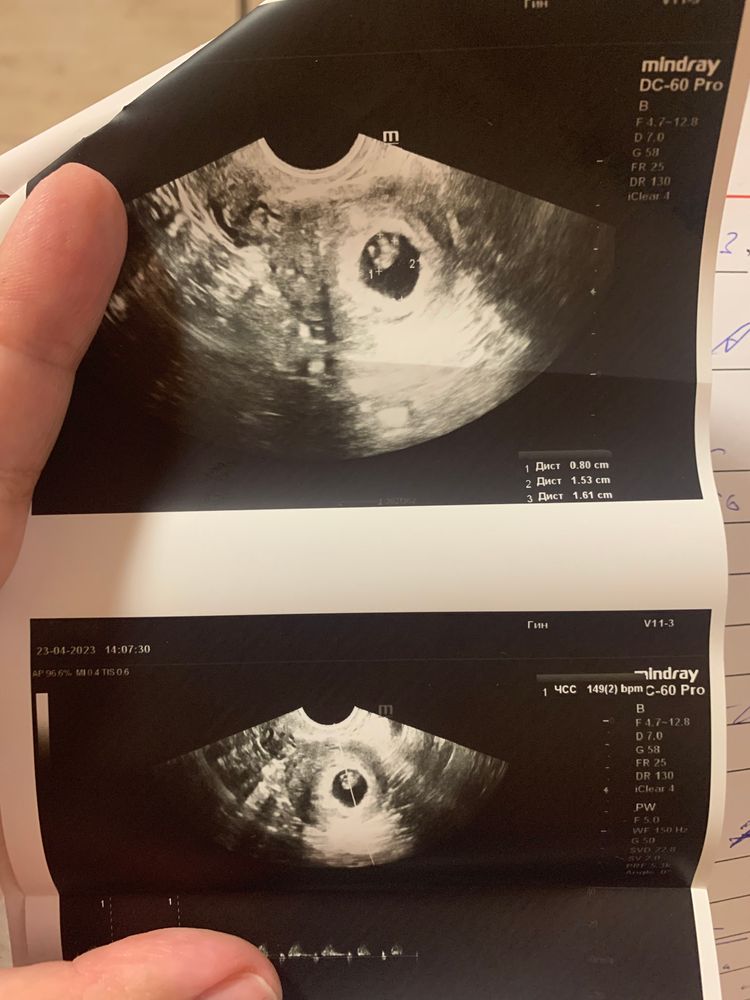

Изображение Помню только что ктр тут 8мм. делала в 7,2 недель